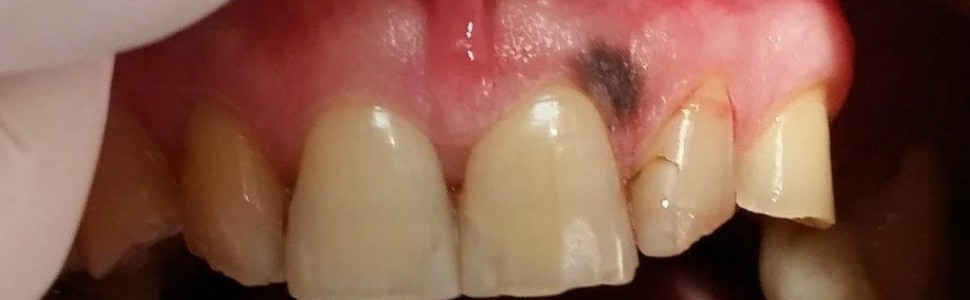

Diagnostyka i leczenie naczyniaka jamistego dziąsła szczęki. Opis przypadku

Celem pracy jest prezentacja przypadku 63-letniego ogólnie zdrowego pacjenta ze zmianą barwną w obrębie dziąsła szczęki. W pracy opisano trudności diagnostyczne zmian barwnych w jamie ustnej oraz przedstawiono schemat postępowania diagnostyczno-leczniczego. W opisanym przypadku wstępne rozpoznanie kliniczne (plama barwnikowa) nie zostało potwierdzone w badaniu histopatologicznym (naczyniak jamisty). Mimo to uzyskano estetyczny i stabilny wynik leczenia chirurgicznego, potwierdzony w obserwacji 7-letniej.

The aim of the study is to present a case of a 63-year-old generally healthy patient with a discoloration within the maxillary gingiva. The paper  describes the diagnostic diffi culties of pigmented lesions in the oral cavity and presents a diagnostic and therapeutic approach. In the described case, the initial clinical diagnosis (melanotic macule) was not confi rmed in the histopathological examination (cavernous hemangioma). Despite this, an aesthetic and stable result of surgical treatment was obtained in a seven-year observation.